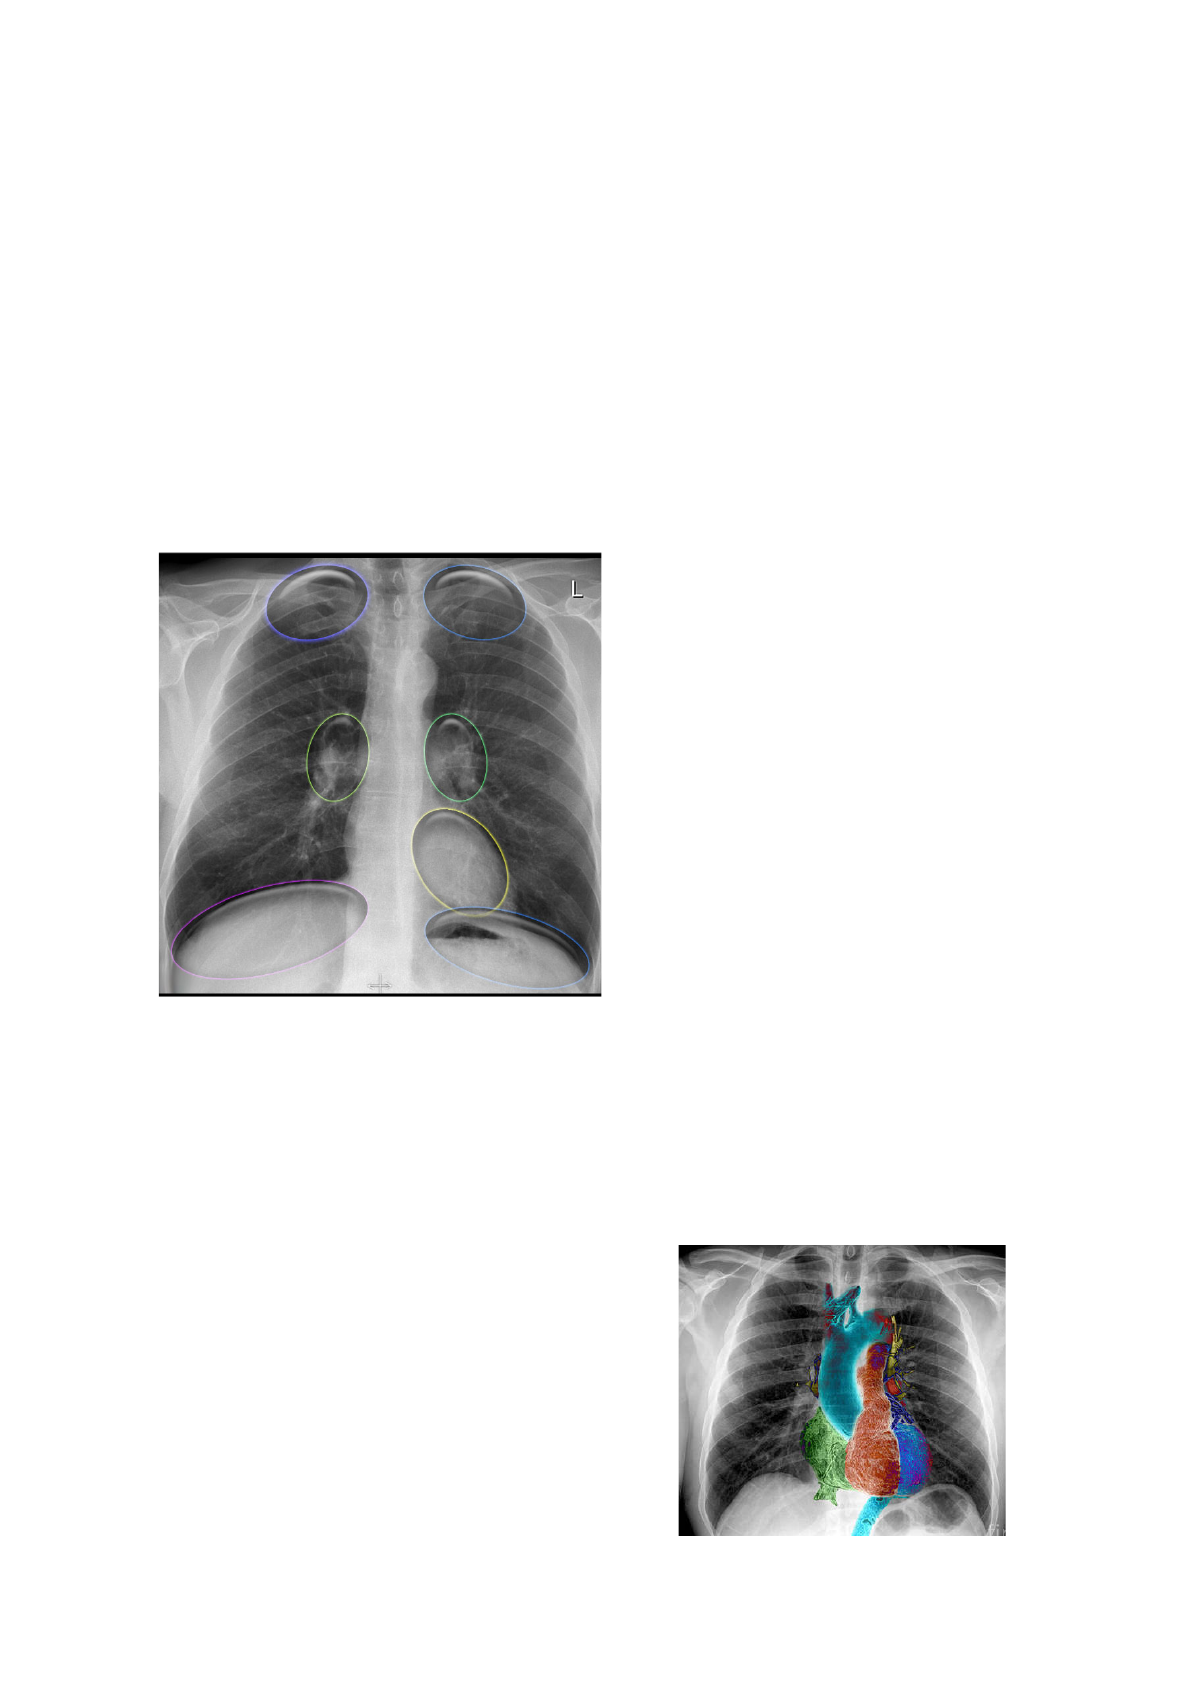

Radiologia Torácica

Áreas Escondidas

Áreas mais difíceis de serem vistas por

sobreposição de estruturas;

Áreas atrás das clavículas, áreas dos

hilos pulmonares, área retrocardíaca e

áreas atrás dos diafragmas;